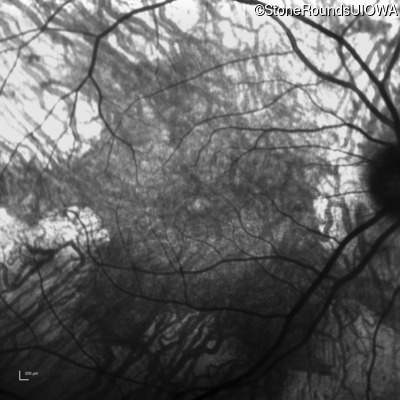

Infrared Fundus Photograph - Left - 20/32 -2

Exemplar